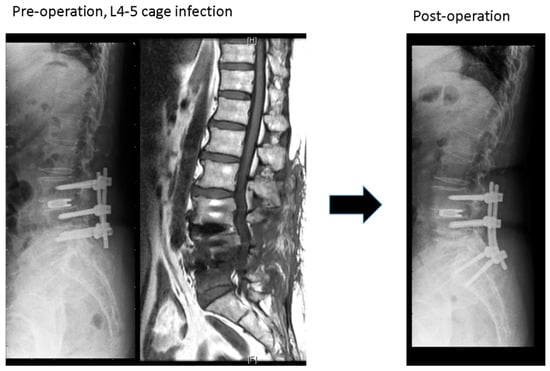

The study group (Figure 1) included 15 patients: 8 women and 7 men with a mean age of 67.2 years. The mean BMI, CCI, and ASA were 25. 4 ± 2.6 kg/m2, 1.8 ± 0.8 and 2.9 ± 0.4, respectively. The mean interval between primary and revision surgeries was 91.5 ± 76.3 days. The L4-5 segment was the most common infection site (10 patients, 66%). The mean operation time and blood loss were 229.5 ± 37.3 min and 427.7 ± 250.3 mL, respectively. Thirteen patients in the study group had positive culture data; Staphylococcus aureus and Staphylococcus epidermidis were the most common pathogens. Eight patients’ infected cages could be removed successfully, but the other seven patients’ cages were retained at where left they were. All these 15 patients’ infections were cured after surgery and intravenous antibiotic treatment, with an average hospital stay of 28 days. Before revision surgery, the mean VAS score was 8.0 ± 0.7, which finally improved to 3.5 ± 1.2. The ODI also improved from 44.2 ± 11.5 preoperatively to 18.5 ± 12.2 finally. The final radiographs showed that six patients achieved grade I fusion, eight patients were assessed as grade II fusion, and one patient’s fusion status was grade IV.

Figure 1. A case in the study group: L4-5 cage infection treated by removal of the L5 screws, extending screw to S1 with contralateral transforaminal debridement and fusion at L4-5 disc space.